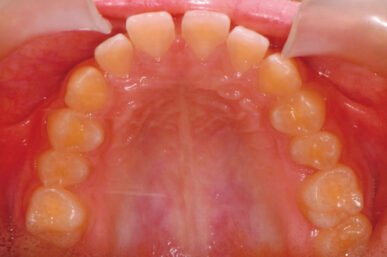

• Before

• After

出っ歯が気になるという事でしたが、下顎がさがっていました。治療開始が遅かったため生え代わりを待つ必要があり、治療期間が長くなりました。

下顎が正しい位置で噛むようになり、出っ歯に見えなくなりました。